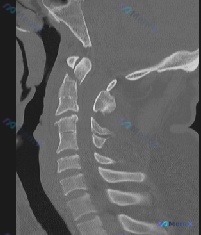

整理到一个上颈椎损伤的病例讨论材料,先看基础信息: - 患者:45岁男性 - 就诊原因:运动交通事故就诊急诊科 - 主诉:颈部疼痛 - 查体:ASIA E(神经功能完好) - 影像:张口颈椎X光片、矢状位CT、CT轴位血管造影 影像分析提示: 1. 枢椎(C2)齿状突基底部骨折,骨折块与椎体分离 2...